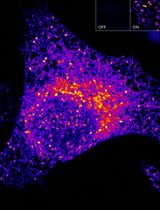

- Illustrated is a double injection protocol that monitors the ability of PYY(3-36) to lower levels of 299 [cAMP] in cells that are treated with forskolin and that express NPY2R (see legend for Figure 4).

Figure 4. Peptide YY(3-36) lowers levels of cAMP in HEK293-NPY2R-H188 c18 cells. A. HEK293/hNPY2R/H188 c18 cells stably expressing the human NPY2R receptor and H188 were allowed to adhere to an RTC-coated reading plate for overnight culture. On day 2 the ability of forskolin alone to raise levels of cAMP was monitored (red trace). Note that this action of forskolin was dose-dependently reduced when the NPY2R agonist PYY(3-36) (1-10 nM) was administered 125 s prior to administration of forskolin using a "double injection protocol". PYY(3-36) binds to NPY2R to activate Gi proteins and to lower adenylyl cyclase activity, whereas forskolin directly stimulates adenylyl cyclase. Thus, this assay monitors the opposing actions of PYY(3-36) and forskolin to control levels of cAMP. Non-linear regression analysis of the data demonstrated that the IC50 for PYY(3-36) action in this cell line was 2.1 nM. Non-linear regression analysis was performed with Origin 8 software using the highest ∆FRET values for each data point. Note that the time scale is 1,200 s, thereby revealing short and long-term actions of forskolin and PYY(3-36) in this assay. B. Converse experiment in comparison to A in which forskolin was administered prior to PYY(3-36) using HEK293/hNPY2R/H188 c18 cells and the double injection protocol. Note that the time scale is 400 s, thereby revealing the fast action of PYY(3-36) (1 μM) to reduce the rate of increase of ∆FRET. This NPY2R-mediated action of PYY(3-36) signifies Gi protein-mediated inhibition of adenylyl cyclase with resultant lowering of cAMP levels, as detected using H188.